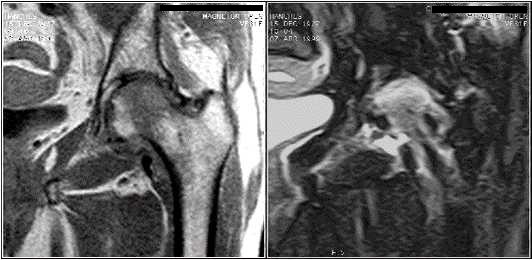

Musculosketal cases